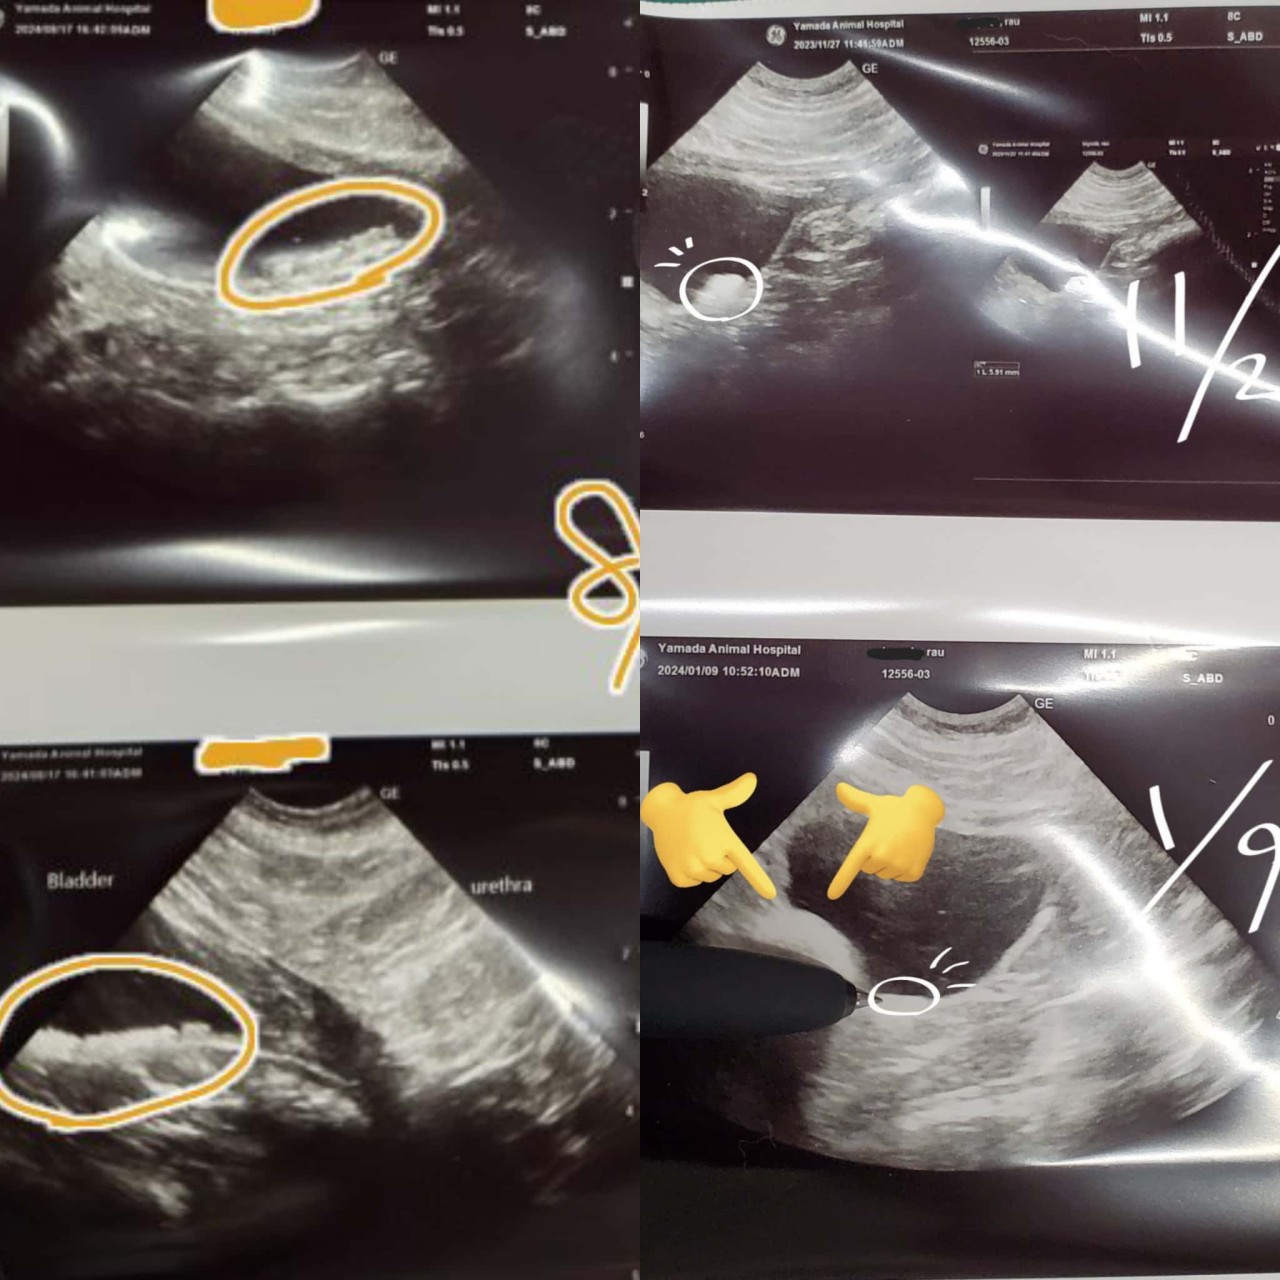

膀胱結石とシコリ

肺のレントゲンと、膀胱&腎臓のエコー。

膀胱の尿結石がまだ消えてなくて、なんなら一月よりレベルアップしてる。

尿ケア食べさせてるのに消えてない→溶けないシュウ酸カルシウム尿石の可能性

ミウちゃんの足の付け根に大きめのシコリ?を発見して虚無です。どうか良性であってくれ~!!